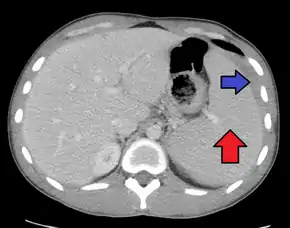

Spleen enlargement is common in the second and third weeks, although this may not be apparent on physical examination. Rarely the spleen may rupture.[23] There may also be some enlargement of the liver.[21] Jaundice occurs only occasionally.[13][24]

Splenomegaly is a common symptom of infectious mononucleosis and health care providers may consider using abdominal ultrasonography to get insight into the enlargement of a person's spleen.[54] However, because spleen size varies greatly, ultrasonography is not a valid technique for assessing spleen enlargement and should not be used in typical circumstances or to make routine decisions about fitness for playing sports.[54]